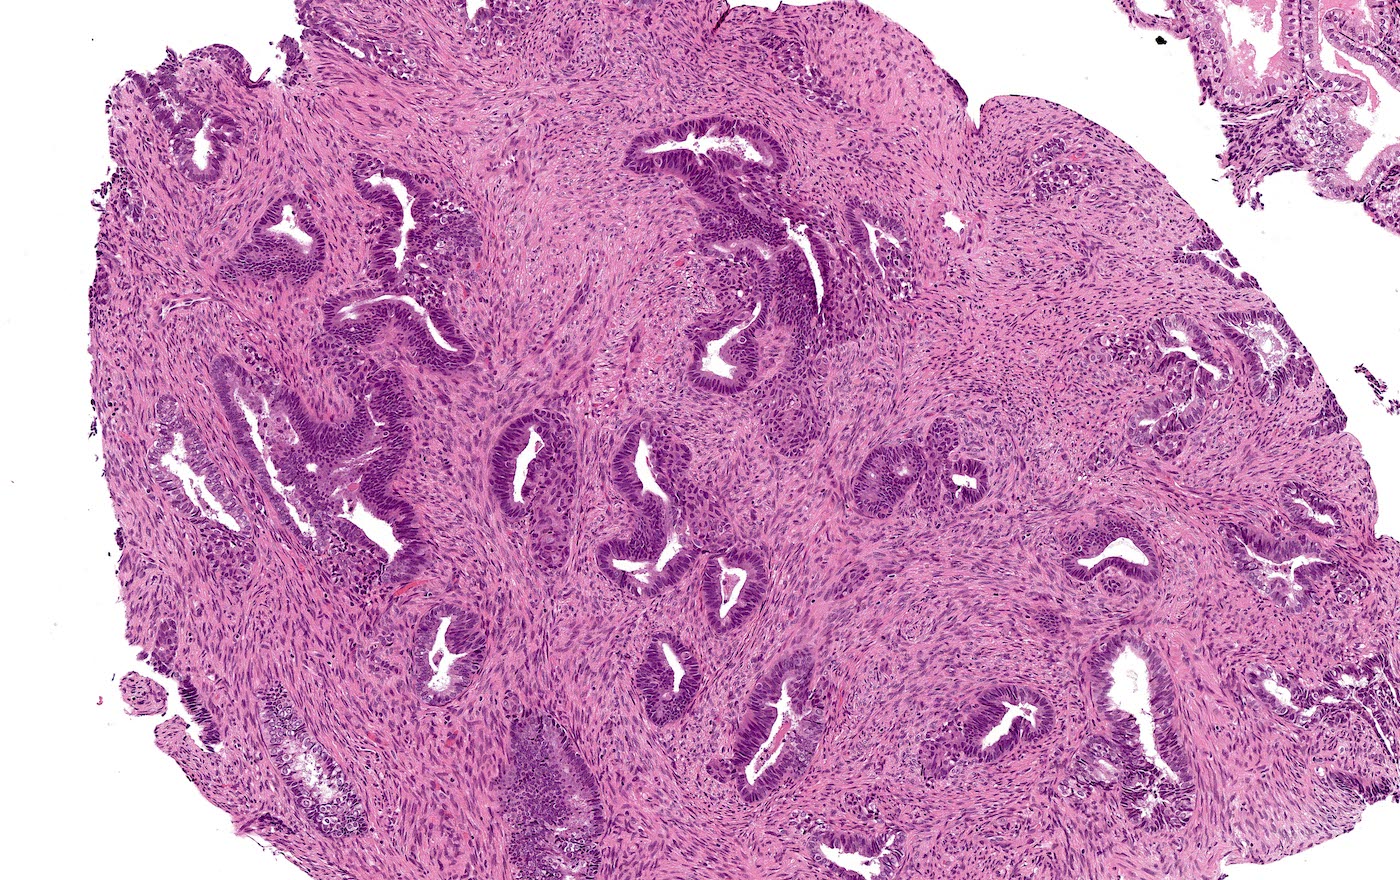

Microscopic (histologic) description

- Biphasic tumor:

- Endometrioid glands, usually with complex architecture and sometimes with cytologic atypia

- Glandular component often shows lobulated architecture

- Benign fibromyomatous stroma, rarely with myxoid change

- Squamous morular metaplasia is frequently seen and may show central necrosis

- Well circumscribed or slightly irregular margin

- Reference: Am J Surg Pathol 2015;39:1148

Microscopic (histologic) images